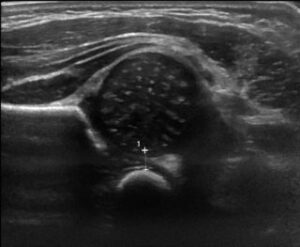

Le dépistage s’effectue à l’âge de 1 mois, en échographie. Il est rapide (quelques minutes) et inoffensif.

Chaque hanche est évaluée.

La mesure du fond cotyloïdien est actuellement la mesure recommandée et validée. Elle est reproductible entre les radiologues et dans le temps.